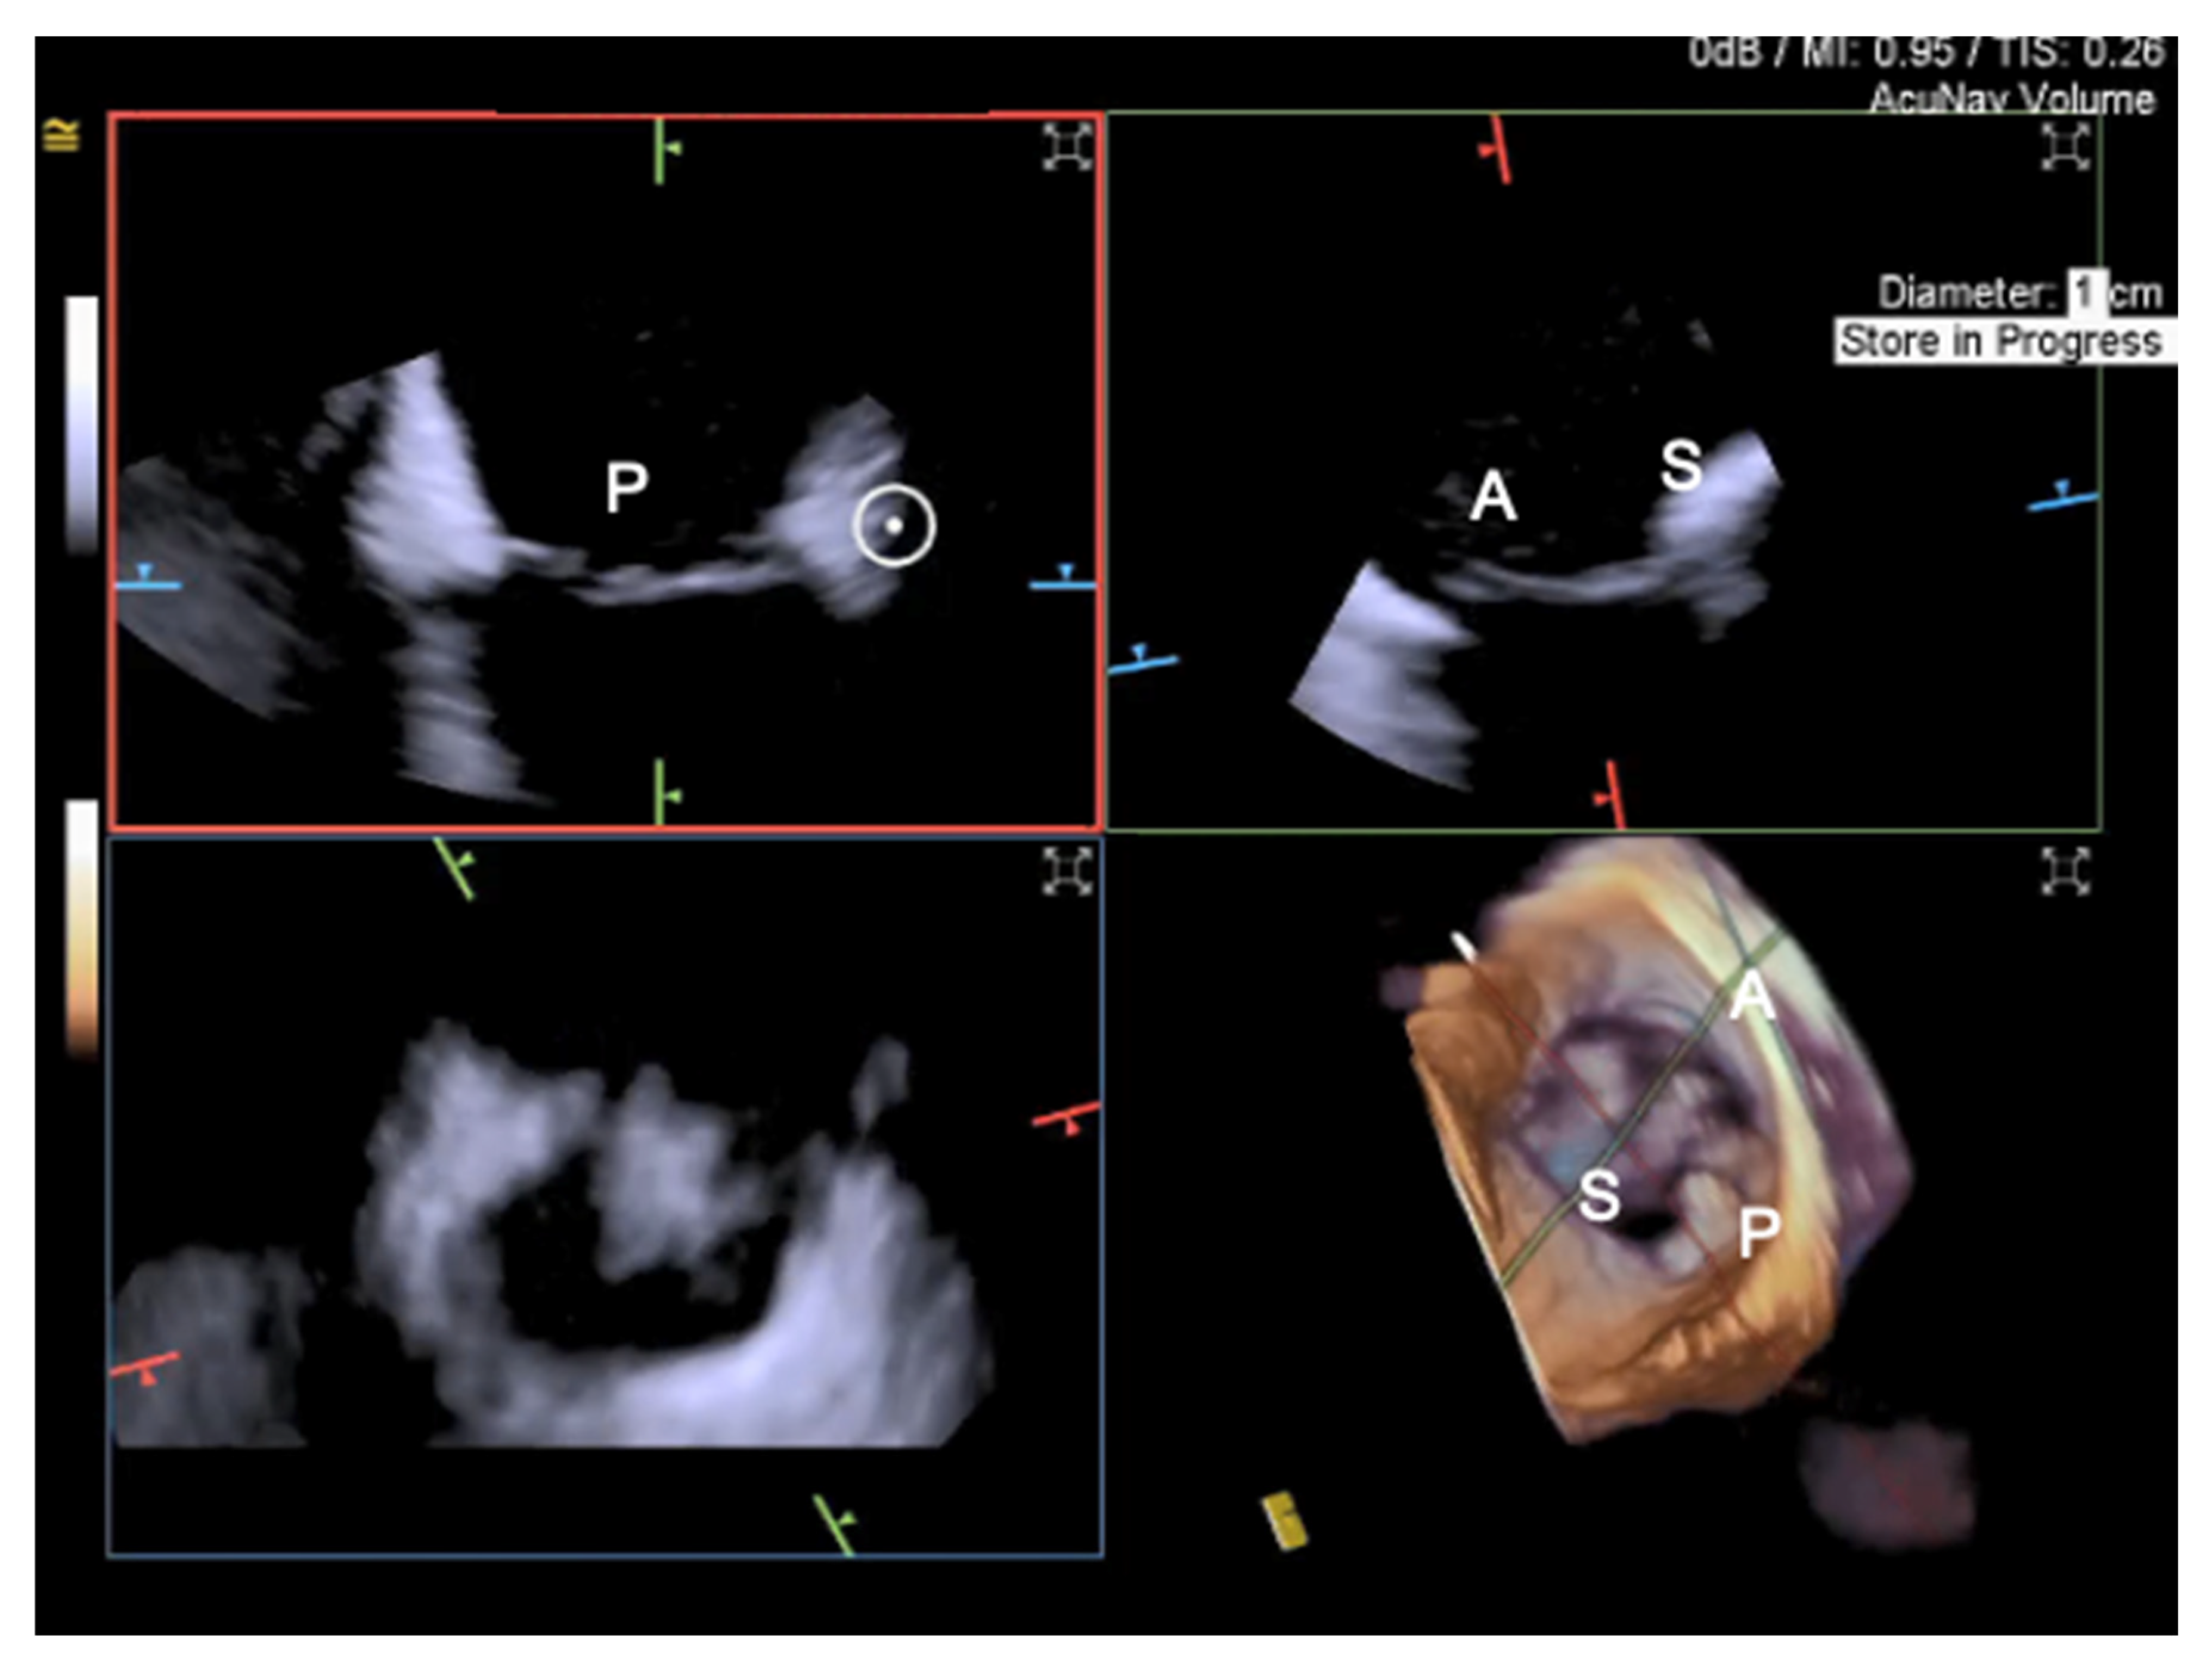

- Tang, G.H.; Yakubov, S.J.; Soto, C.E.S. 4-Dimensional Intracardiac Echocardiography in Transcatheter Tricuspid Valve Repair with the MitraClip System. JACC Cardiovasc. Imaging 2020, 13, 1591–1600. [Google Scholar] [CrossRef]

- Silvestry, F.E.; Kadakia, M.B.; Willhide, J.; Herrmann, H.C. Initial experience with a novel real-time three-dimensional intracardiac ultrasound system to guide percutaneous cardiac structural interventions: A phase 1 feasibility study of volume intracardiac echocardiography in the assessment of patients with structural heart disease undergoing percutaneous transcatheter therapy. J. Am. Soc. Echocardiogr. 2014, 27, 978–983. [Google Scholar] [CrossRef]